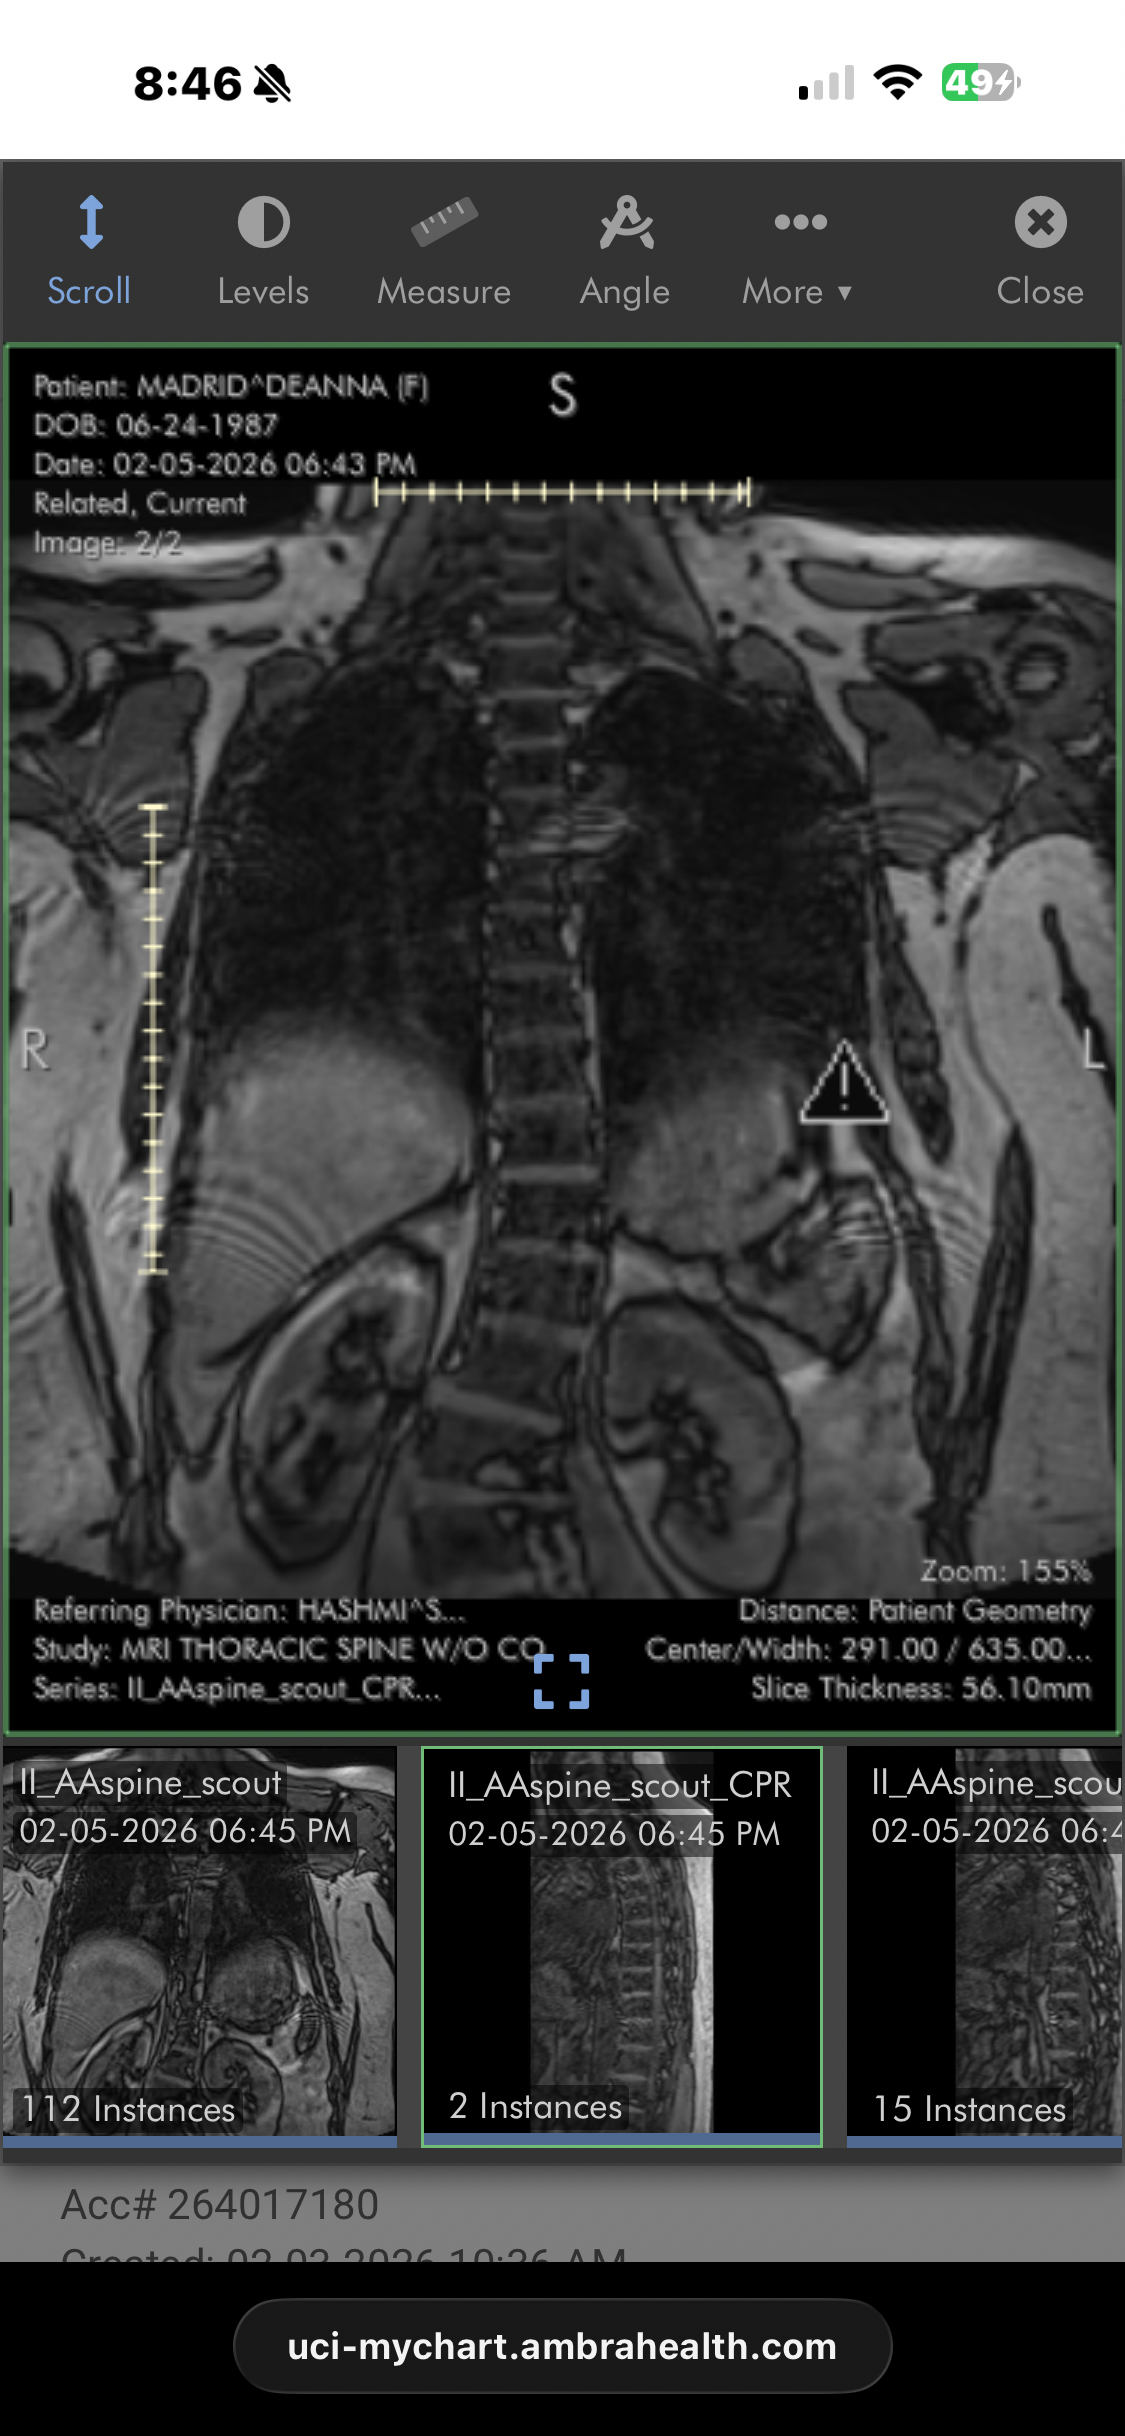

I'm 38 years old and have been suffering with lupus, POTS, and degenerative scoliosis for 13 years. It's been a long road of ups and downs, with various hospitalizations, expensive treatments, and many challenges just trying to live life at times. There have been moments of joy and good health, but each flare-up seems more difficult than the last. This time, my mobility is greatly impacted—I'm unable to sit up for long, walk, or stand for very long. The pain has left me unable to work, and I'm facing an extensive lumbar fusion surgery from T12-L4. I'm scared, but hopeful that this surgery will finally end the majority of the pain I've lived with for so long, and that I can get back to helping patients working in healthcare, which I truly miss.